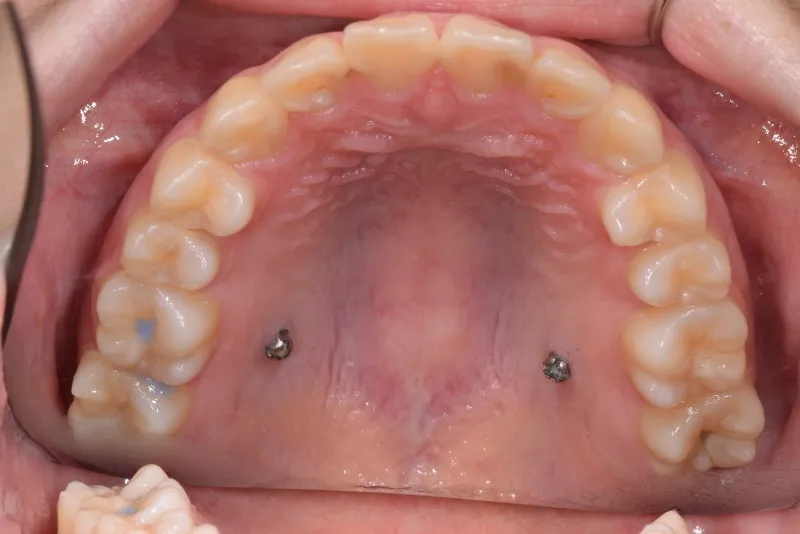

治療終了後

乳歯があるうちは上下オリジナル固定装置を利用し、永久歯が生えそろったらマルチブラケット装置を利用して治療しました。

治療回数35回、5年9ヶ月の治療期間で矯正治療を終了しました。